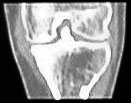

Immerhin scheinen meine Knochen eine Art Schnellheilungsmechanismus zu haben: Nur 5 Wochen nach der Korrekturoperation ist der Knochen schon fast wieder ganz verheilt - im folgenden Bild aus dem Inneren des Knies ist links das Bild vom 3. Mai, rechts jenes vom 7. Juni. Das versetzte Stück der Eminenz ist fast wieder fest drin; die Lücke beim Pfeil hat sich deutlich verkleinert - Krücken ade, Schmerzen leider noch nicht ganz. Das Streckdefizit beträgt immer noch 12 Grad.